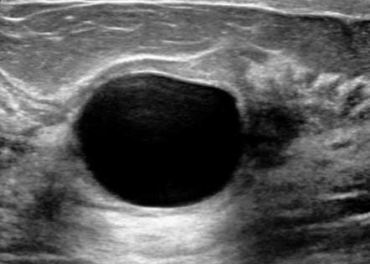

At Ultracare Diagnostic, we understand the importance of your health and the essentiality of accurate diagnosis. Therefore, we offer you comprehensive care and a non-invasive Ultrasound test that helps determine how well your body organs are functioning and if there are any abnormalities present. This helps the doctor to provide you with an accurate diagnosis and treatment for the same

We offers Best Services With Experienced hand on Sonology